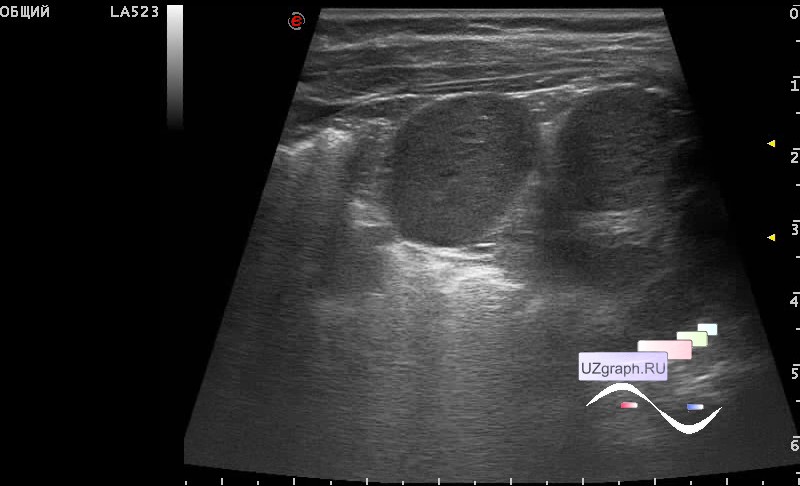

Как выглядит доля Риделя на УЗИ печени